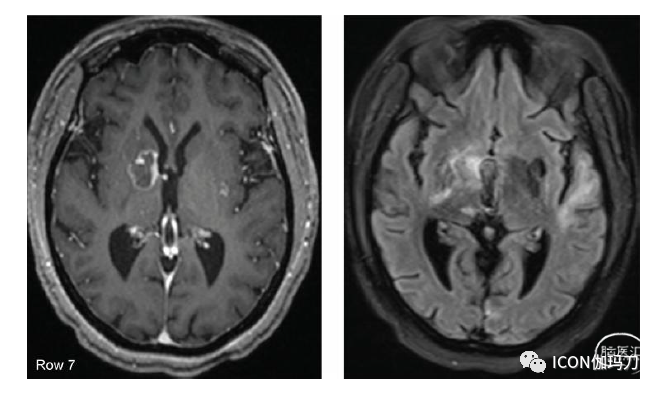

对于不太容易外科手术接近的病变,一种更近期的外科技术称为激光热凝固术(laser thermocoagulation)或激光间质热治疗(laser interstitial thermotherapy,LITT)已经发展起来,以满足组织诊断和治疗放射性坏死的需要。自十年前推出以来,它被越来越多地使用,包括在标准开颅手术可治疗病变的患者中。这部分是因为该技术的微创性,尽管在大多数中心,这些患者仍然需要全身麻醉。在此过程中,在头皮上做一个小的刺入切口和在颅骨上做一个5毫米的钻孔,以帮助病变活检首先提供诊断。然后,沿着相同的轨迹,病变可以使用二极管激光进入病变中心进行消融。激光发出的光在周围的组织中转化为热。然后使用连续术中MR梯度回波成像监测热传递的进程。然后使用专有软件计算实时消融图,利用每个成像体素处于升高温度的时间,使外科医生能够监测并确定消融何时完成(图36.5)。术后患者通常需要在夜间观察,由于切口小且没有开颅手术,很少需要疼痛管理。大多数患者可以在术后第一天回家。

图36.5(第1排)肺癌患者在接受18 Gy的 SRS治疗后1年维持TKI,且右侧基底神经节病变再次生长。(第2行)在LITT手术开始时,激光纤维被立体定向地放置在肿瘤中间(白色轮廓)。上面3排是消融图,黄色圆圈显示从激光光纤周围开始热扩散的位置。(第三排)手术后期,黄色圆圈表示热通过病灶扩散。(第4行和第5行)LITT治疗消融完成时在治疗软件窗口和标准解剖平面估计区域的黄色轮廓包围肿瘤。(第6行)LITT后2周T1加权钆剂增强和 MRI的FLAIR序列显示强化病灶大小稳定,脑水肿早期减少。(第7行)LITT治疗后6周,病灶尺寸减小,周围脑水肿减少。